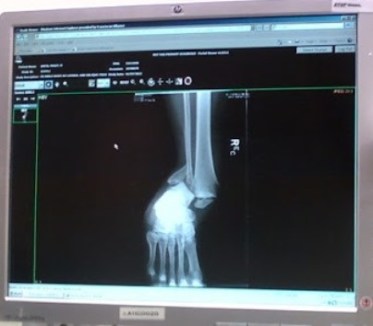

January 2013 – My wife Peggy slipped on some ice and broke her right ankle. It was a compound fracture that laid her up for over six months. It was a stressful time…loss of half her wages, hospital bed in the living room, multiple surgeries and follow-up visits (in the winter)…you get the picture. She was in a lot of pain during most of this time, and her ankle will never be the same. Arthritis has set in, and her cartilage is gone.

The ER x-ray of Peggy’s fractured right ankle.